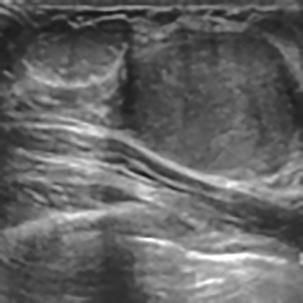

乳腺癌是全球女性最常见的恶性肿瘤之一,准确的病变分割对于乳腺癌的早期诊断与治疗具有重要意义。然而,由于病变形态的多样性以及超声成像机制的复杂性,现有基于深度学习的乳腺超声图像病变分割方法在分割准确性方面仍面临巨大挑战。为进一步提升乳腺超声图像中病变区域的分割精度,该文基于经典U-Net架构,提出了一种新型乳腺超声图像病变分割网络(CWSASKM-BBAM-Net)。首先,在网络中引入逐通道空间自适应选择核卷积模块(CWSASKM),根据不同通道的语义特征为每个空间位置自适应选择感受野大小,以增强多尺度信息的建模能力;然后,引入双向边界感知机制(BBAM),通过融合正向与反向注意力,对目标显著区域及其边界进行协同建模,同时逐步提升对非显著区域与病变区域的区分能力,以进一步强化边界信息的表达;最后,在3组公开乳腺超声图像数据集(BUSI、UDIAT和STU)上开展分割实验。结果表明:该方法在数据集BUSI上的杰卡德指数、精确率、召回率和Dice相似系数分别为71.97%、82.85%、81.40%和80.44%,较次优方法分别提升1.69、1.05、1.28和1.84个百分点;在数据集UDIAT上,这4项指标分别达到78.14%、88.31%、86.73%和86.10%,较次优方法分别提升了2.75、2.04、0.56和2.01个百分点;在外部数据集STU上,该方法也取得了优于其他方法的整体表现。实验结果表明,CWSASKM-BBAM-Net在乳腺超声图像分割任务中展现出更优的整体性能。